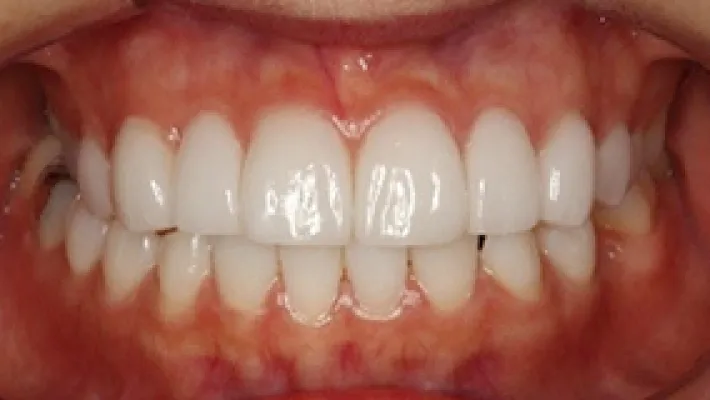

施術前

施術後

マウスピース矯正の部分矯正で上下前歯のすきっ歯を改善した症例です。

状態にもよりますが、すきっ歯はマウスピース矯正の得意とするケースの一つです。

効率的な治療計画で最小限の期間と負担で矯正を行いました。

矯正治療の期間・方法

矯正治療の期間や方法は歯並びや顎骨などの状態によって大きく異なります。

矯正治療は歯や歯周組織などに必ずダメージがあります。

矯正治療のダメージを最小限にするために健康的で現実的な治療計画を提案します。

治療費

420,000

治療期間

4.5ヶ月